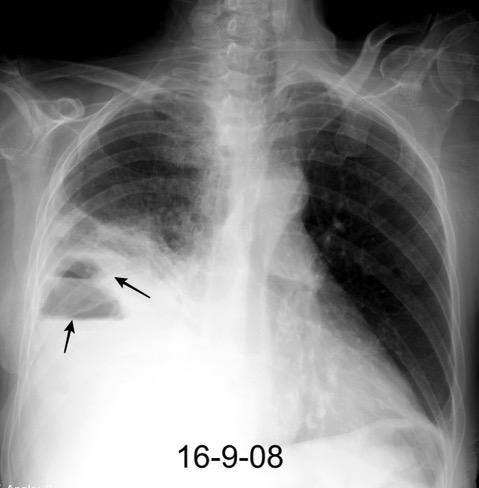

Marzo 2014: Perforación longitudinal distal secundaria a episodio de vómito (síndrome de Boerhaave). Derrame pleural izdo. que evoluciona a empiema.

Wang C-T et al. Tension hydropneumothorax in a Boerhaave syndrome patient: A case report . World J Emerg Med, 2021. Katabathina V et al. Nonvascular, nontraumatic mediastinal emergencies in adults:a comprehensive review of imaging findings. Radiographics. 2011.